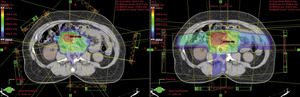

Teleradioterapia, napromienianie wiązkami zewnętrznymi, jest prowadzona głównie przy użyciu wysokoenergetycznych fotonów X, generowanych w przyspieszaczach liniowych. W wybranych sytuacjach mają też zastosowanie wiązki elektronów o różnie dobieranych energiach. Coraz rzadziej stosowane jest promieniowanie gamma kobaltu 60. Postęp technologiczny i dostępność komputerowych systemów planowania przestrzennego radioterapii, opartych na nowoczesnych technikach obrazowania, umożliwiły w większości ośrodków planowanie radioterapii dostosowawczej (konformalnej), realizowanej według indywidualnie przygotowanych planów leczenia. Planowanie pól napromieniania odbywa się przestrzennie – trójwymiarowo (3D), z wykorzystaniem przekrojów tomografii komputerowej, na których lekarz oznacza guz nowotworowy, elektywny obszar do napromienienia (regionalne węzły chłonne z adekwatnym marginesem) i narządy krytyczne (ryc. 1). W wybranych przypadkach w planowaniu wykorzystuje się połączenia obrazów z badaniem pozytonową tomografią emisyjną (PET-TK), co daje możliwość zwiększenia dawki w obszarze dużej aktywności metabolicznej guza nowotworowego lub jego przerzutów do regionalnych węzłów chłonnych (ryc. 2).1,2 Za pomocą komputerowych systemów planowania leczenia fizyk tworzy indywidualny plan leczenia, który powinien spełniać kryteria jednorodnego rozkładu dawki promieniowania w planowanej objętości napromienianej (PTV) oraz dużego gradientu dawki poza tą objętością. Jednocześnie nie należy przekraczać ustalonych dawek tolerancji w narządach krytycznych (OR) (ryc. 3). Dopasowanie kształtu pola napromieniania do konturu planowanej objętości napromienianej osiąga się, stosując kolimatory wielolistkowe o zmiennym kształcie. Poprawność planowania radioterapii oparta na kryteriach zebranych w raportach 50 i 62 International Commission on Radiation Units (ICRU) dokumentują histogramy rozkładu dawki promieniowania w planowanej objętości i w wybranych narządach krytycznych (ryc. 4). Ośrodki wyposażone w nowoczesne wysokoenergetyczne przyspieszacze liniowe i wysoko wydajne systemy planowania radioterapii mogą stosować radioterapię z użyciem modulacji intensywności dawki promieniowania (intensity modulated radiation therapy, IMRT). Główną zaletą tej techniki jest możliwość modelowania dawki całkowitej promieniowania w obszarze napromienianym z oszczędzeniem struktur krytycznych (ryc. 5).3 Technika dwuwymiarowa (2D) stosowana jest nadal z powodzeniem w przypadkach leczenia paliatywnego. Stosuje się wówczas najprostsze techniki dwu pól przeciwległych i czteropolową technikę „box”, polegającą na napromienianiu odpowiednio na dwa lub cztery pola wlotowe, których płaszczyzny są parami równolegle. Powyższe napromienianie nie gwarantuje jednak jednorodnego rozkładu dawki promieniowania w wyznaczonej objętości. Stwarza ono też ryzyko przedawkowania ponad należną dawkę promieniowania w obrębie narządów krytycznych.